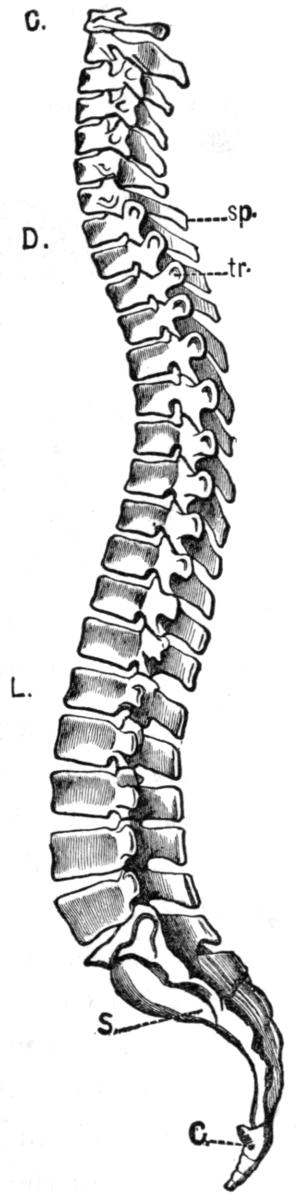

| III. | The Skeleton | H 28 |